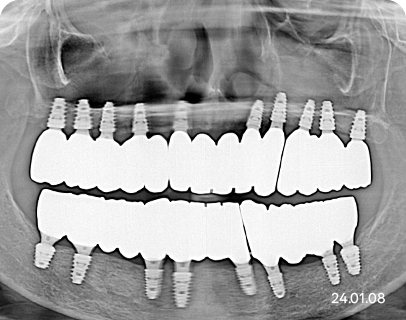

전체 임플란트 식립 예시

최대 식립 | 총 19개

절충형 식립 | 총 14개

최소 식립 | 총 12개

세종스타치과는 꼭 필요한 자리에만, 꼭 필요한 개수로 전체 임플란트 식립 치료를 진행합니다.